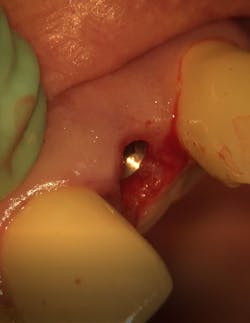

- Treatment plan: Extraction/immediate implant placement with nonfunctional provisional

- Implant: Ditron Ultimate 3.75 x 16 mm

- Abutment: Final straight 11.5 mm titanium abutment delivered at time of implant placement